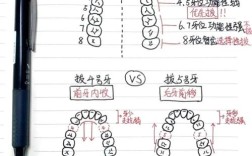

牙齿拥挤是最常见的错颌畸形之一,主要源于颌骨发育空间不足与牙齿数量、大小的矛盾,正常情况下,每颗牙齿需要一定的“生态空间”,当颌骨长度无法容纳所有牙齿时,就会出现牙齿重叠、扭转、错位,上颌牙弓长度不足时,侧切牙可能萌出不全(埋伏或过小),前牙向唇侧突出形成“龅牙”,后牙可能因拥挤而扭转,影响清洁甚至导致龋齿,拔除1-4颗前磨牙(通常为第一或第二前磨牙),可为剩余牙齿提供排齐所需的空间,通过正畸技术(如滑动机制或关闭曲),牙齿会向拔牙间隙缓慢移动,最终达到整齐排列的状态,这一过程需严格遵循牙槽骨改建规律,确保移动过程中牙齿周围组织稳定,避免损伤。

咬合异常包括深覆盖(上前牙突出超过下前牙)、深覆合(上前牙盖过下前牙过多)、反合(下前牙咬在上前牙外侧,即“地包天”)等,不仅影响美观,还可能导致咀嚼效率下降、颞下颌关节紊乱(如张口弹响、疼痛)、牙齿磨损等问题,以深覆盖为例,常因上颌前突或下颌后缩导致,若不拔牙,单纯内收前牙空间不足,可能无法改善侧貌甚至加重突度;拔除上下颌前磨牙后,可利用拔牙间隙整体内收上下前牙,调整牙轴倾斜度,使前牙覆盖关系正常,后牙咬合接触点分布均匀,恢复咀嚼功能,对于反合患者,若存在牙列拥挤,拔牙可解除拥挤,为后牙移动建颌创造条件,纠正反合。

部分患者存在颌骨发育不协调,如下颌后缩伴上颌前突,导致“凸面型”;或上下颌牙弓宽度不匹配,导致面部不对称,拔牙可通过调整牙齿位置,间接影响颌骨与面部的协调性,在双颌前突病例中,拔除上下颌前磨牙后,通过内收前牙,减少唇部突度,改善侧貌轮廓;对于牙弓狭窄患者,拔牙后可配合扩弓技术,调整牙弓宽度,使面部比例更协调,拔牙还能为“骨性畸形”患者提供正畸-正颌联合治疗的基础,通过正畸移动牙齿至理想位置,再通过手术调整颌骨,最终实现功能与美学的统一。